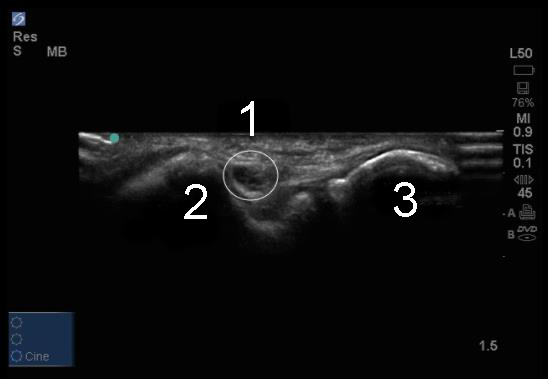

肘の肘部管の横断画像

尺骨神経

内側上顆

肘頭突起